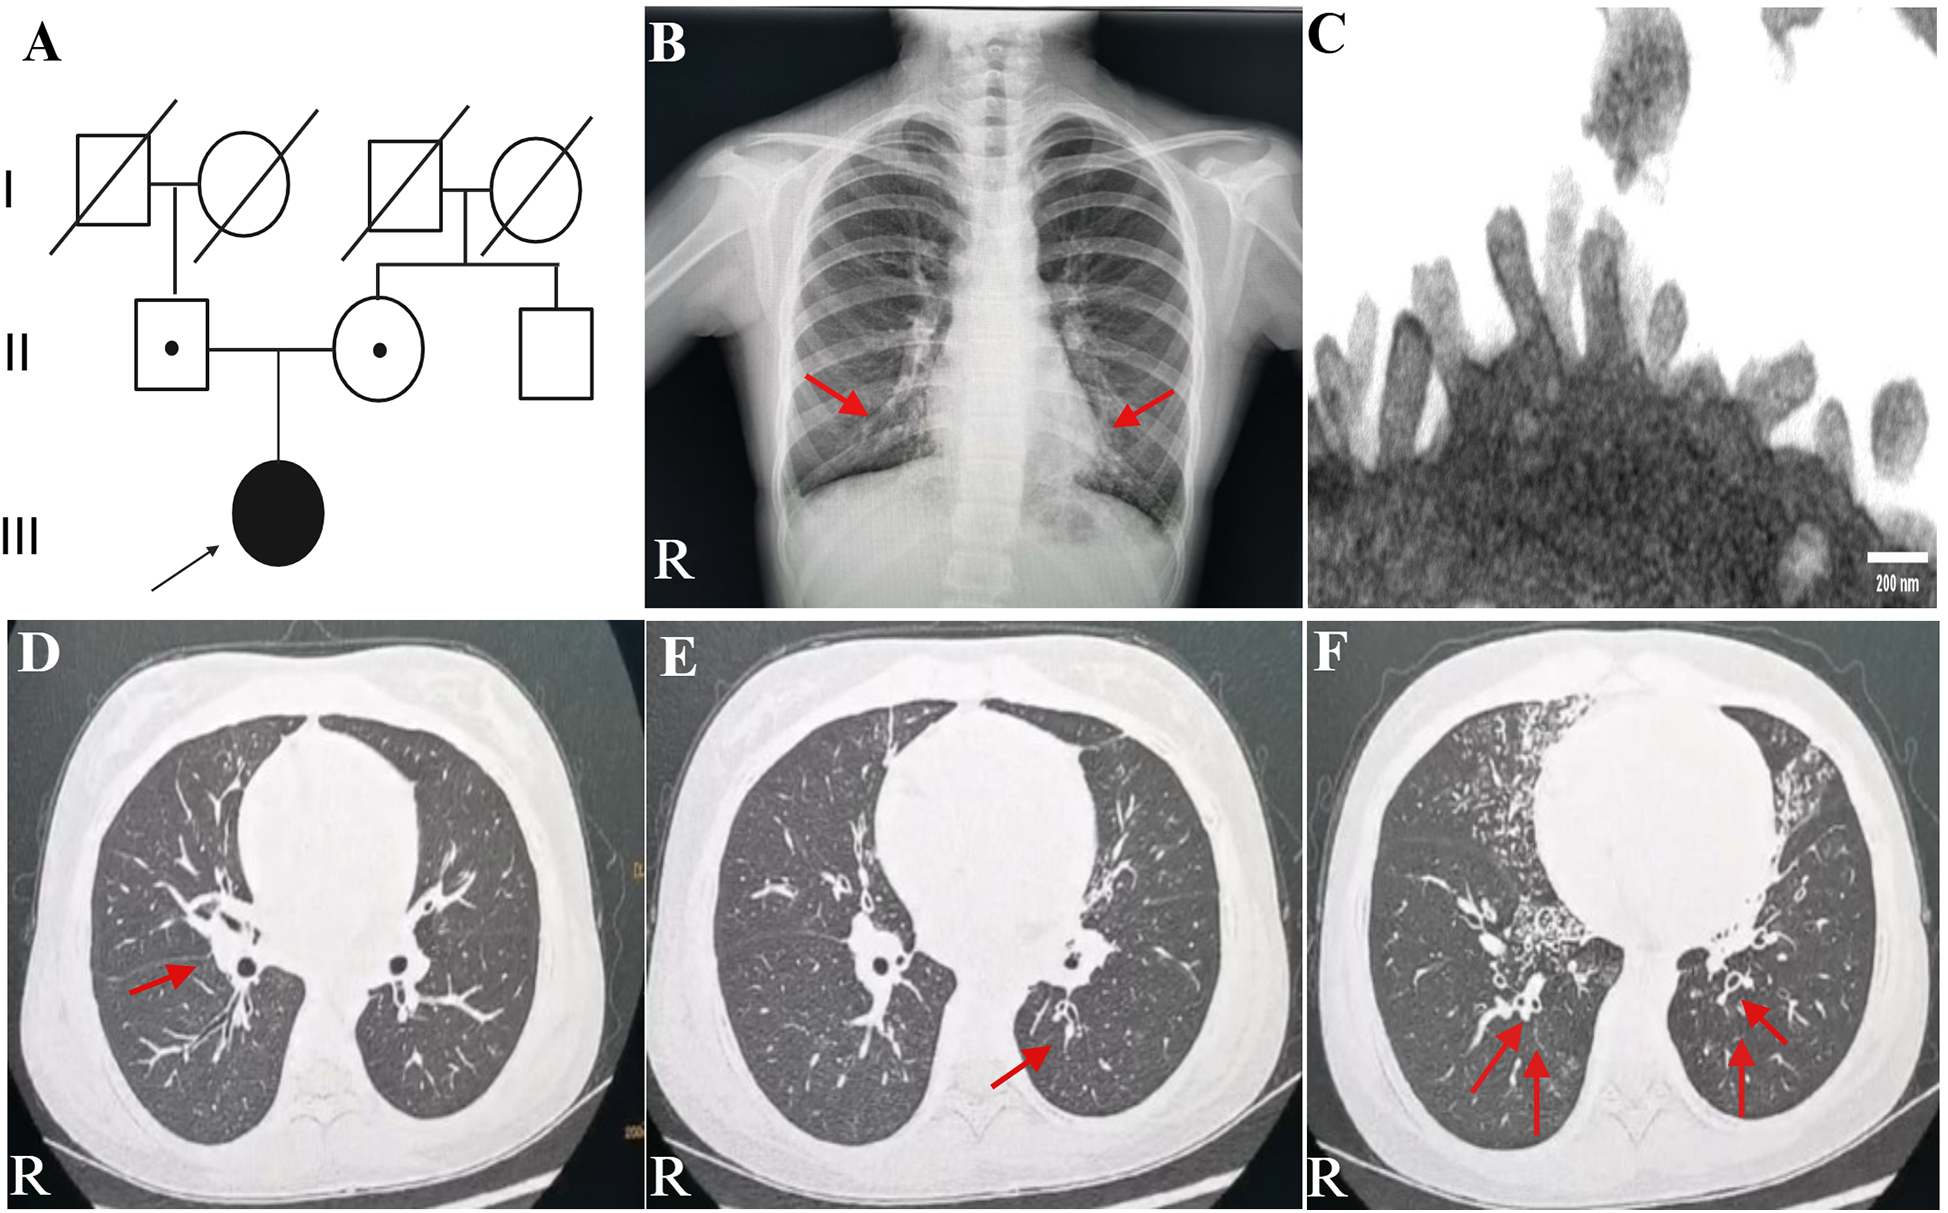

A teenage girl, aged 11 years and 3 months, was admitted to the respiratory department of our hospital with a 1-week history of cough and 1-day history of fever. She came from a non-consanguineous family, according to the family history, and her parents showed no symptoms (Figure 1A). Born at term, the patient was admitted to a neonatal unit and diagnosed as neonatal pneumonia at 24 h after birth. She had no history of prolonged oxygen dependency and displayed situs solitus. She had persistent perennial rhinitis and a recurrent productive cough since she was 7 years old. She takes montelukast orally every day and continuously inhales powdered budesonide and formoterol fumarate. Additionally, the patient was diagnosed with sinusitis and secretory otitis media by the otolaryngologist based on nasal obstruction, purulent nasal discharge for over 4 years, and the results of the otoscopy examination. Her motor, cognitive, and language development was normal, with no hydrocephalus. At 11 years old, she was admitted to our respiratory department for community-acquired pneumonia. Chest radiograph indicated bilateral pleural thickening and inflammation of lower fields of both lungs (Figure 1B). Bronchoscopy revealed a lot of white and viscous secretions in the bronchial cavities bilaterally. A bacterial culture of bronchoalveolar lavage fluid (BALF) exhibited Pseudomonas aeruginosa. Transmission electron microscope (TEM) showed microvilli with few cilia on the epithelial surface (Figure 1C). Electrocardiogram, echocardiography, myocardial enzymes, liver and kidney function tests, plasma electrolytes, serum mycoplasma and chlamydia antibodies, and immunoglobulin levels were unremarkable.

Figure 1. Family history and clinical characteristics of the patient. (A) This PCD patient came from a non-consanguineous family, and her parents showed no clinical symptoms. The teenage female proband inherited a homozygous mutation from both heterozygous carrier parents. The proband is identified by the arrow. (B) Chest radiograph indicated bilateral pleural thickening, inflammation of lower fields of both lungs, and no ectopic heart. Inflammation infiltration images are shown by the red arrows. (C) TEM indicated microvilli on the epithelial surface. (D–F) Axial view: lung CT scan indicated infections in the middle lobe of the right lung and the lower lingual segment of the upper lobe of the left lung and inflammation of lower lobes of both lungs, with slightly dilated bronchi in the lower lobes of both lungs. As is shown by the red arrows. PCD, primary ciliary dyskinesia; R, right; TEM, transmission electron microscope.

A lung CT scan indicated infections in the middle lobe of the right lung and the lower lingual segment of the upper lobe of the left lung and inflammation of the lower lobes of both lungs, with slightly dilated bronchi in the lower lobes of both lungs (Figures 1D–F). The first-time pulmonary function (PF) test showed increased airway resistance and decreased ventilation function of small airways, with forced vital capacity (FVC) at 82.9% of the predicted value, forced expiratory capacity in 1 s (FEV1) at 78.5% of the predicted value, peak expiratory flow rate (PEF) at 58.0% of the predicted value, and forced expiratory flow at 75% of forced vital capacity with 50.2% of the predicted value. Multiplex combined detection of respiratory pathogens testing of BALF was positive for P. aeruginosa DNA and Streptococcus pneumoniae DNA and negative for Mycobacterium tuberculosis DNA. Her fractional exhaled nitric oxide (FeNO) level was 5.8 ppb. The nasal nitric oxide (nNO) was measured at 16.0 ppb (9.6 nl/min). The patient no longer had a fever following 1 week of intravenous ceftriaxone infusion, 3 days of oral azithromycin anti-infection treatment, and 5 days of glucocorticoid inhalation; however, the patient continued to experience recurrent wet coughing. The second-time PF test exhibited that the flow velocity of medium and small airways decreased, and the function of small airways was impaired. Re-examination showed FVC at 94.9% of the predicted value, FEV1 at 86.1% of the predicted value, PEF at 82.2% of the predicted value, and forced expiratory flow at 75% of forced vital capacity with 34.8% of the predicted value. The second time of FeNO measurement was 8.0 ppb, and nNO was 7.0 ppb (4.2 nl/min). PFs and fractional nitric oxide examination results are illustrated in Figure 2.